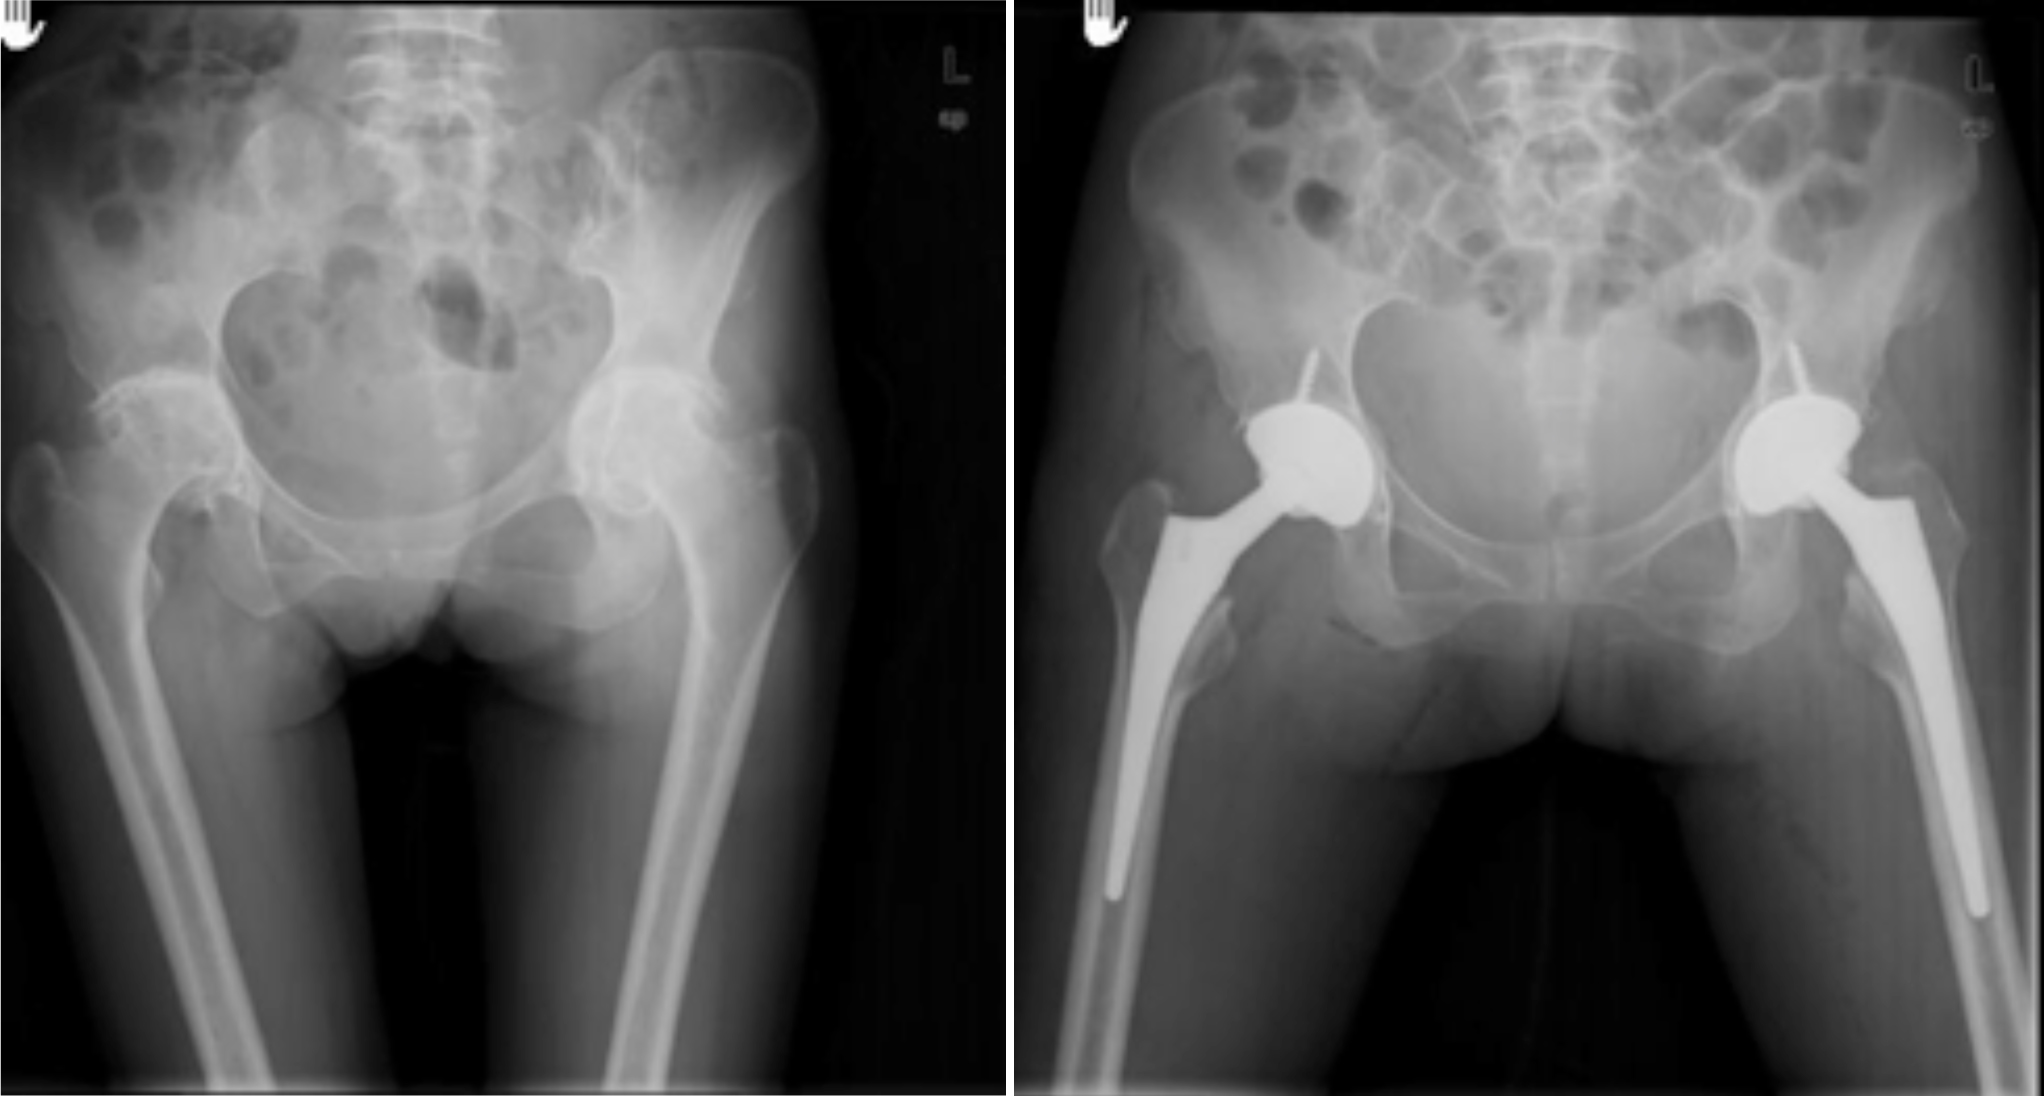

股骨头缺血性坏死

髋关节发育不良

强直性脊柱炎双髋强直

股骨颈骨折

一、人工关节置换 各种晚期骨关节病的关节置换手术治疗是北京清华长庚医院关节外科中心的一大特色,包括股骨头坏死、髋膝骨关节炎、类风湿关节炎、强直性脊柱炎、髋关节发育不良、关节强直、超过80岁的超高龄股骨颈骨折患者的关节置换手术等,我中心在人工关节初次置换及翻修上作了大量工作,置换的难度和手术效果方面已达到国际先进水平,导航下全膝关节置换术:大大提高膝关节置换手术的精确度。